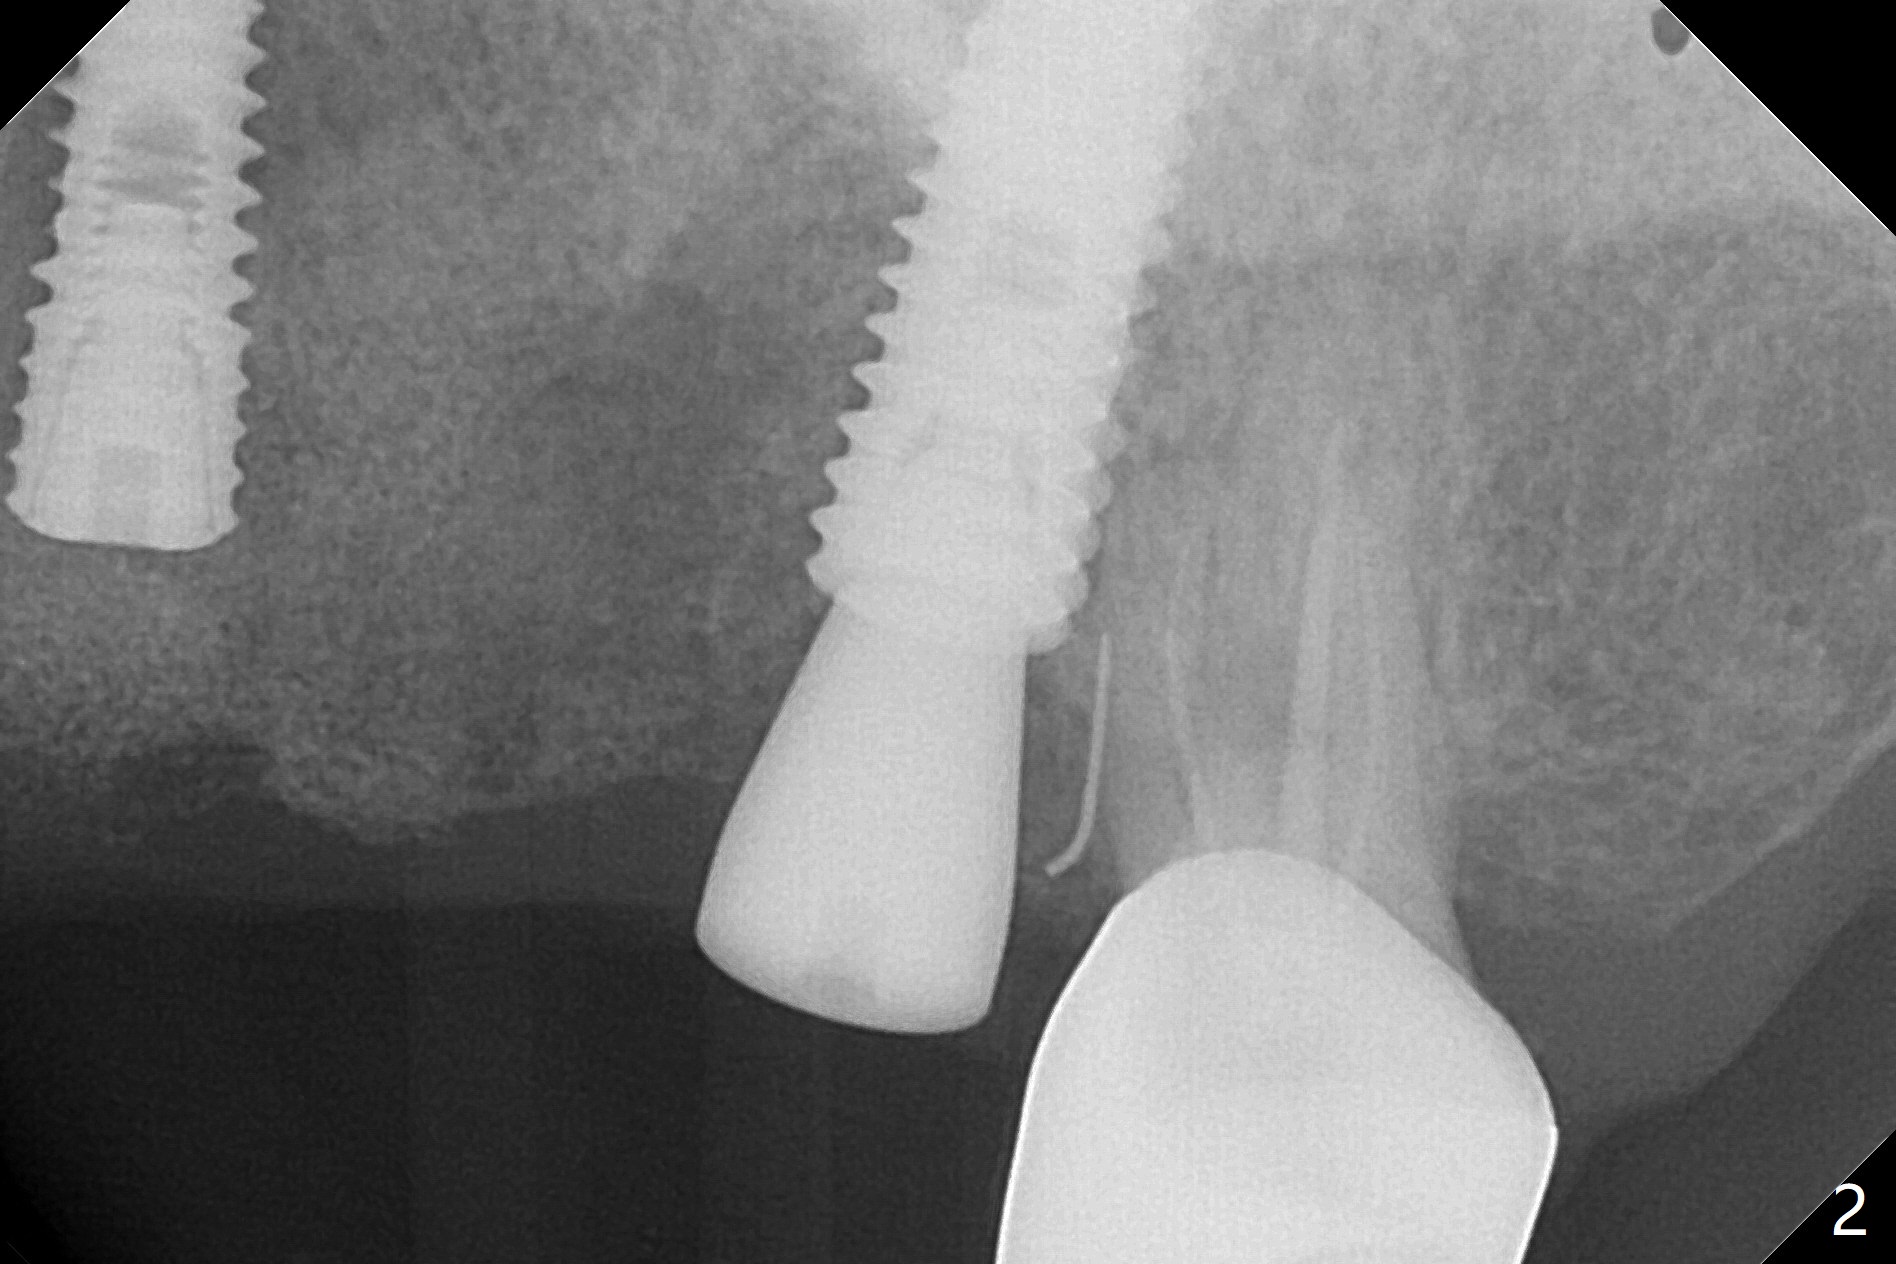

A 55-year-old woman had Hiossen implants (4x13, 5x13 mm) placed at #12 and 14 in China > 6 months (Fig.1,2). The fixtures are placed deep and un-parallel mesiodistally. After SRP UL, the implant at #12 is uncovered, followed by 4.6 and 5.5 mm profile drills and 5.5x7 mm IS healing abutment. The healing abutment at #14 is changed from 5x7 mm to 6.8x7 mm for easy impression later on. Due to coronavirus, the patient returns 8 months later. Oral hygiene is poor. The gingival cuffs at #12 and 14 are erythematous and edematous. UF cemented abutments have to be placed (Fig.3-5) because of equi-gingival fracture of #3 and 4 splinted crowns. In fact the straight abutments are not parallel buccopalatally. Buccoocclusal reduction is done at #12 for provisional FPD. SRP will be performed with #11 DL composite prior to impression.